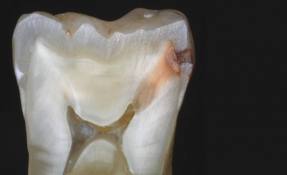

.jpg) Diş Çürükleri: Video-www.youtube.com/watch Diş çürüğü nedir? Diş çürükleri daha çok koyu renklenmelerle birlikte görülen oyuklar olarak algılanmaktadır. Önlenebilir bir hastalık olmasına karşın dünyada diş çürüğü deneyimi yaşamayan çok az insan vardır. Dişler neden çürür? Ağızda bulunan bakterilerden oluşan bakteri plağı, şekerli ve unlu yiyeceklerin ağızda kalan artıklarından asit oluşturabilmektedir. Bu asitler, dişlerin mineral dokusunu çözerek dişin minesinin bozulmasına ve sonuçta da diş çürüğünün başlamasına ve dişhekimlerinin kavite dedikleri oyuklara neden olmaktadırlar. Kimlerde daha çok çürük olur? Şekerli ve unlu yiyeceklerle bakterilerin buluşması sonucunda çürükler oluştuğuna göre herkes için bir tehlike var demektir. Ancak beslenmelerinde karbonhidratlı ve şekerli yiyeceklerin oranı çok yüksek olanlar bir de sularında florür oranı çok düşükse çok daha fazla çürük tehlikesi altındadırlar. Bakteri plağı tarafından oluşturulan asite karşı tükürük doğal bir savunma mekanizması oluştursa da tek başına çürüğü önleyemez.Tükürük akışını ve miktarını azaltan hastalıklar ya da ilaçlar da çürük oluşumunu hızlandırmaktadırlar. Bu nedenle de dişhekimleri tükürük akışını arttırdığı için şekersiz sakızları sıklıkla önerirler. Diş çürüğü önlenebilir mi? Evet. 1. Sabah kahvaltısından sonra ve akşam yatmadan önce dişlerin fırçalanması ve hergün diş ipliğinin düzenli kullanılması en etkili yoldur. Yiyecek artıkları en çok dişlerin çiğneme yüzeylerindeki girintilerde ve dişlerin birbirine değdiği ara yüzeylerde biriktiği için, diş fırçaları küçük başlı seçilmelidir. Dişlerin iç yüzeyleri, dış yüzeyleri, çiğneyici yüzeyleri ve dilin üstü fırçalanmalı ve ara yüzlerde diş ipliği kullanılmalıdır. Fırçalar, orta derecede sert ya da yumuşak kıllı olmalı ve belirli aralıklarda değiştirilmelidirler. Fırça kıllarının aşınmamış olması ve bakteri taşımayacak bir şekilde muhafaza edilmesi gerekmektedir. Asla başkasının diş fırçası kullanılmamalıdır. Diş fırçalama sırasında florürlü bir diş macunu kullanılarak, florürün diş çürüğünü önlemedeki rolünden yararlanılmalıdır. Florürlü macunlara yardımcı olarak aynı zamanda ağız kokusunu gidererek ferahlık ve temizlik hissi veren florürlü gargaralar da kullanılabilir. 2. Şekerli yiyecekleri ana öğünlerde tüketmeye çalışmak ve yemek aralarında birşey yememeye gayret etmek de diğer bir önlemdir. 3. Dişhekimine muntazam aralıklarla başvurmak bir çürüğü önlemek ya da erken yakalamada en iyi yoldur. Ayrıca sıcak ve soğuğa duyarlı dişler ya da ağrılı dişlerde veya tebeşirimsi renkte olan başlangıç çürükleri, kahverengi renklemeler ve oyuklar gibi durumlarda vakit geçirilmeden hekime başvurulması tedavinin şeklini değiştirecek ve zorluğunu azaltacaktır. .jpg)